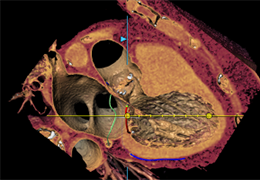

High-quality and fast 3D reconstruction and 3D rendering

Performs 3D reconstruction and volume rendering.

Oblique slicing.

Axis-aligned cropping with context.